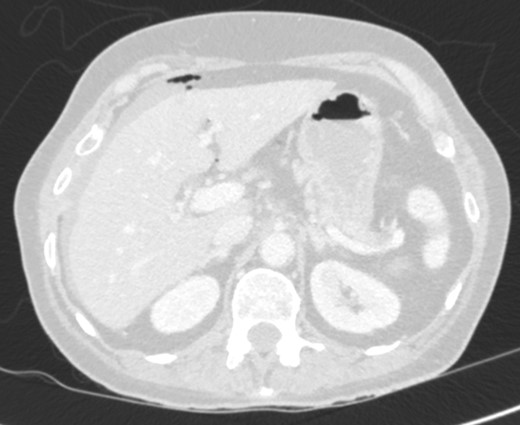

On examination, she was febrile. Her abdomen was generally tender. Bowel sounds were present and up to that time her stoma was working. Her perineal hernia was red and tender. Her initial CXR (Fig. 1) did reveal a sliver of gas underneath her right hemidiaphragm and in keeping with her abdominal findings she progressed to further imaging. CT abdomen pelvis with contrast showed pneumoperitoneum (Fig. 2) with ‘a tiny pocket of air is also seen adjacent to a loop of bowel in the pelvis posterior to the bladder’. ‘Exact site of perforation has not been demonstrated but could possibly be in the bowel loops in the perineum’ (Figs 3 and 4).

Sagittal view showing small bowel loops in pelvis with perineal hernia.